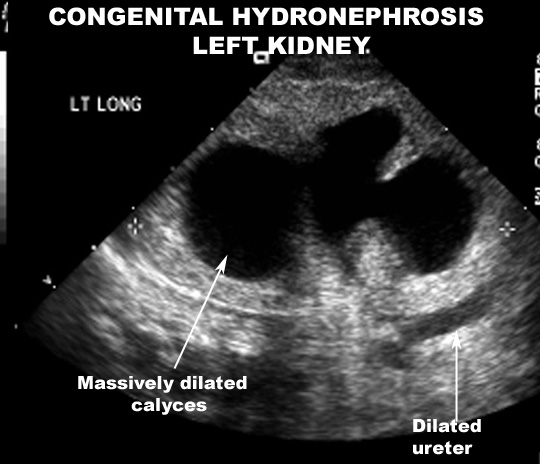

Findings in Ultrasound:

- Dilatation of calyces and pelvis

- Renal parenchymal thickness decreased